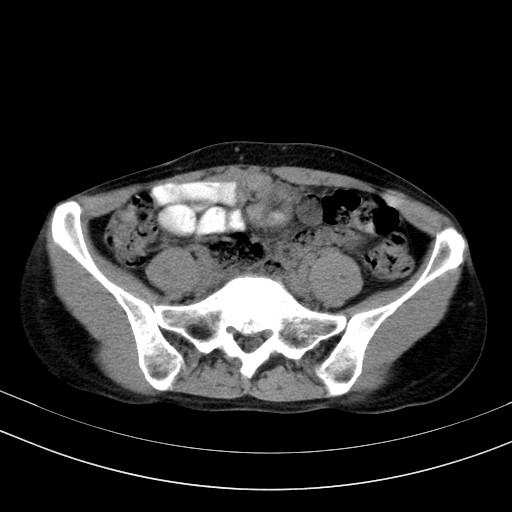

以下是引用随光逐影在2009-4-7 8:17:00的发言:[br]考虑宫颈占位性病变(宫颈癌?);建议行进一步检查。

以下是引用jiangjing在2009-4-7 16:46:00的发言:[br]宫颈增大,结构不清,右侧附件区可疑囊样占位,建议增强及mri 检查